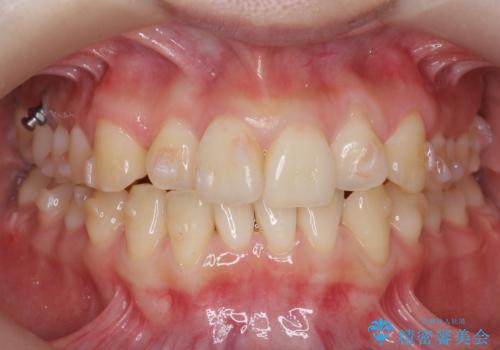

前歯がねじれている 奥歯を後ろに下げて歯を抜かずに並べました

- 前歯のねじれを主訴に来院。

前から2番目の歯がねじれて下の歯の内側に入っていました。

また、奥歯のかみ合わせが上の奥歯が若干前に並んでおり、それで前歯が入りきらずにねじれていました。

歯を抜かずに奥歯を後ろに下げてマウスピースで矯正しています。

奥歯を後ろに下げるために、矯正用インプラントを使用しています。